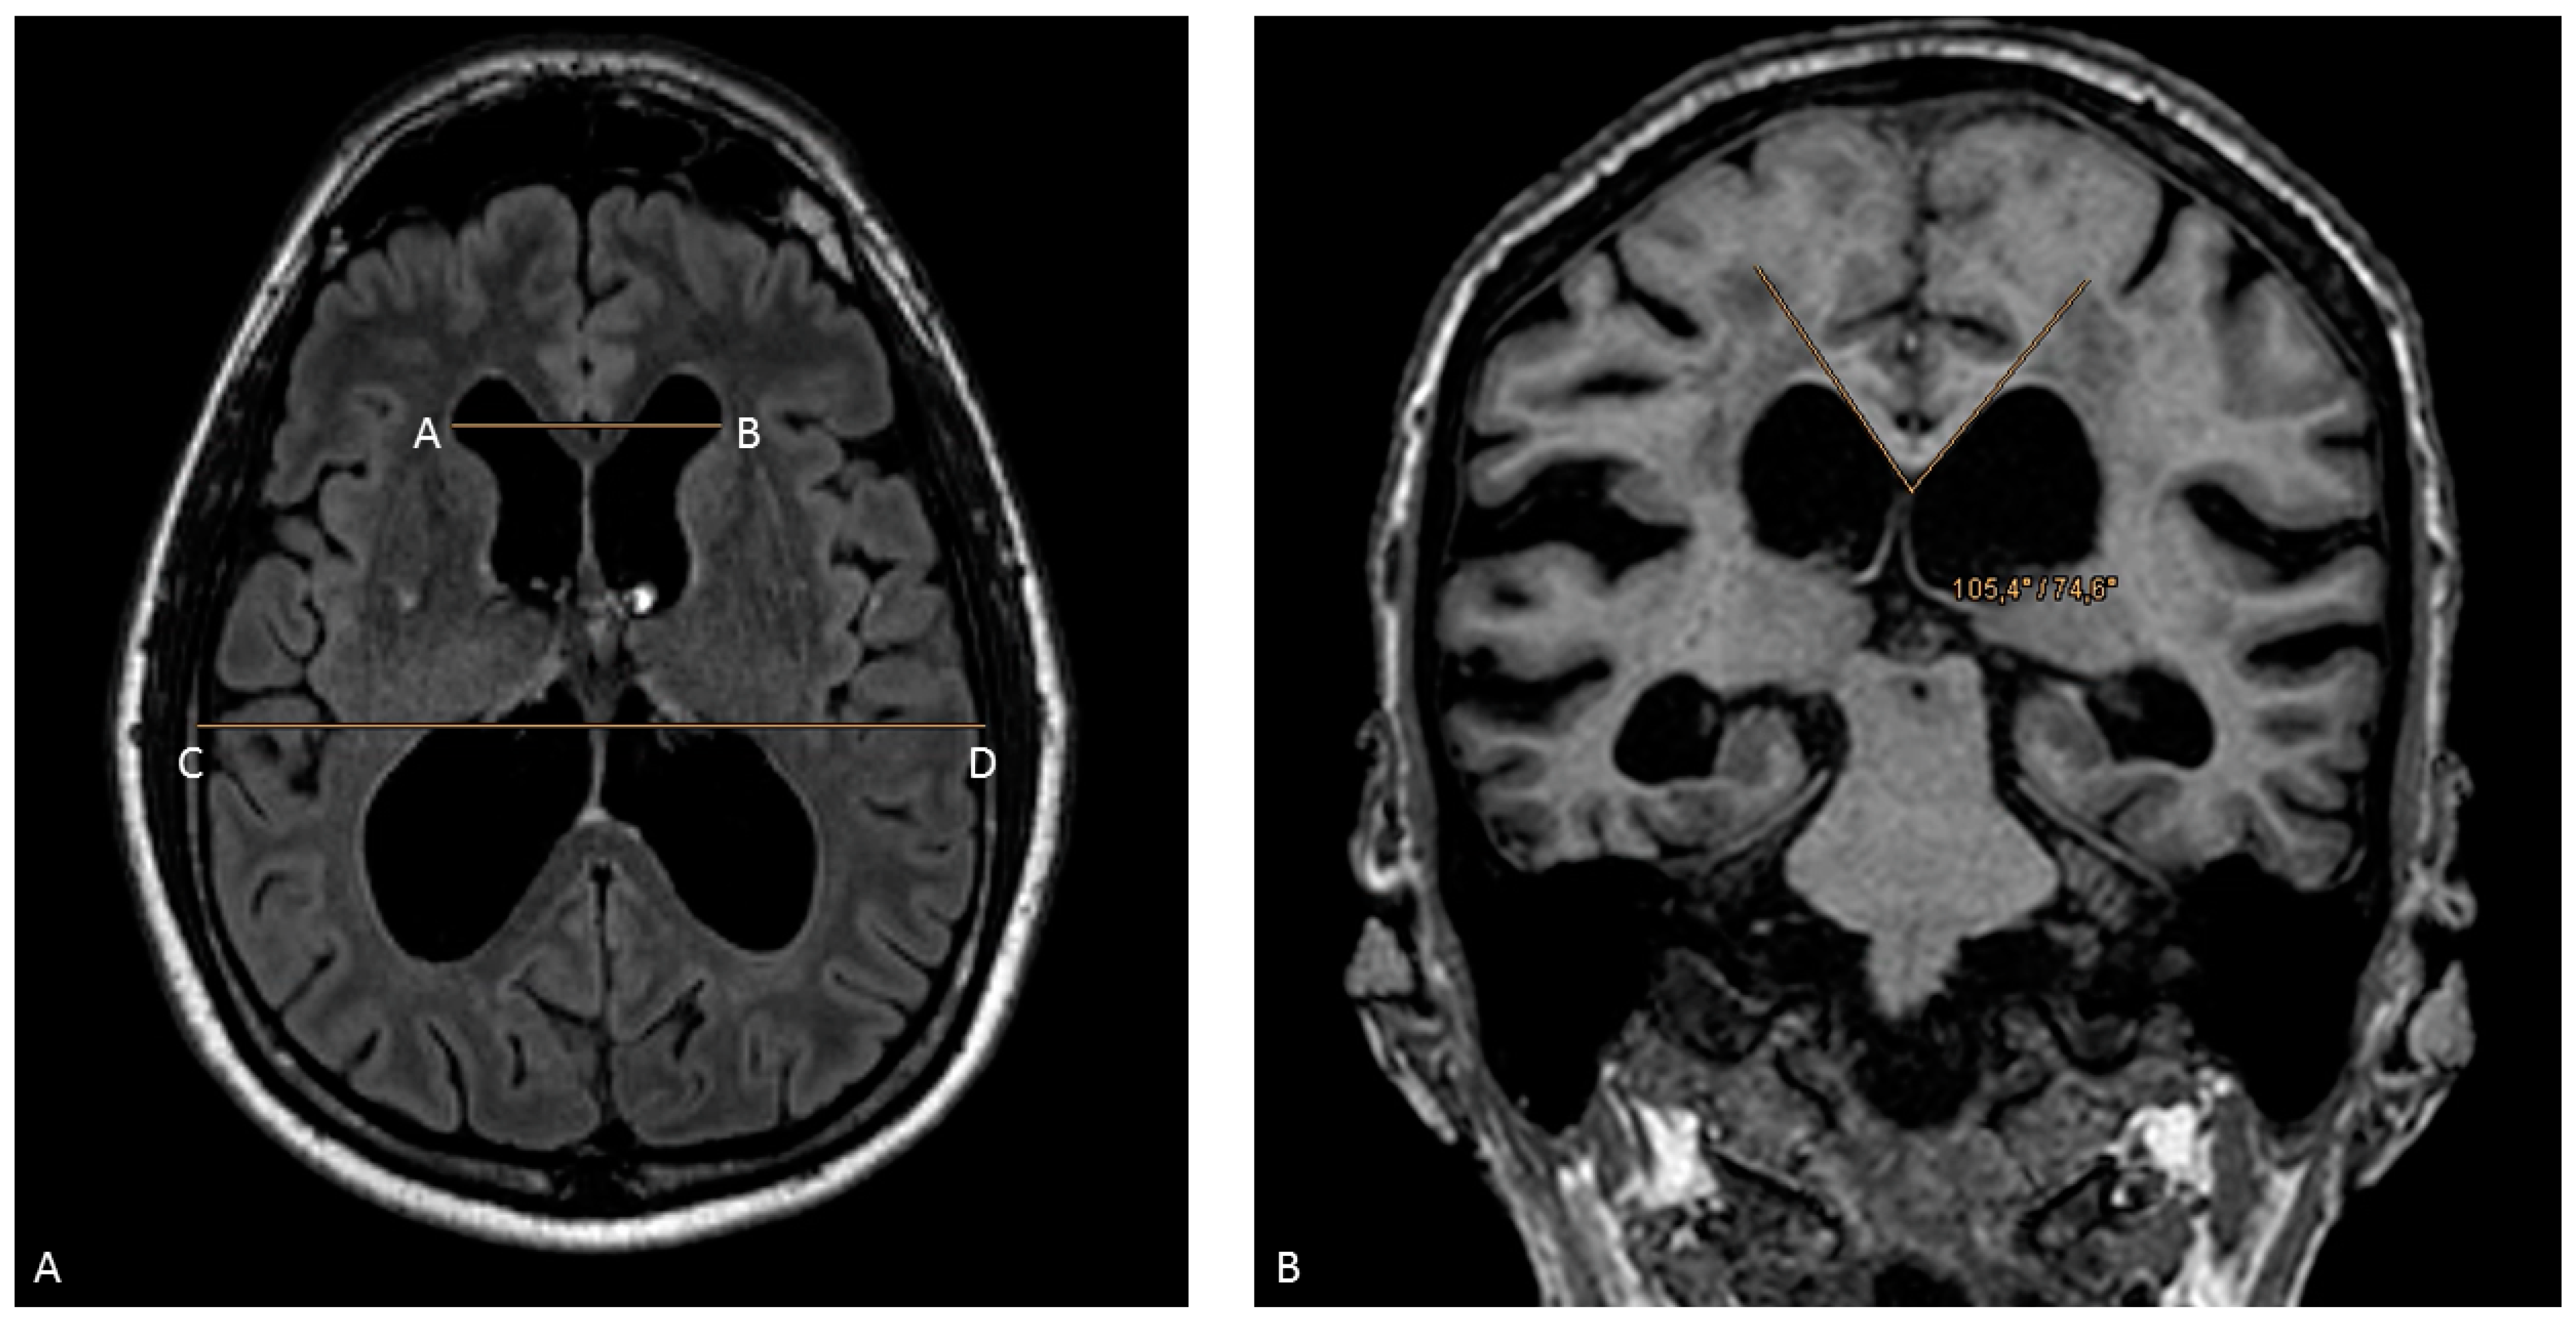

- Imaging characteristics of hydrocephalus with disproportionated enlargement of the ventricles in comparison to the outer subarachnoid spaces, whereby an Evans’ index >0.30 was indicative of iNPH on computed tomography (CT) or magnetic resonance (MR) imaging;

- Callosal angle of <90°;